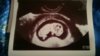

MegaJestem już po usg prenatalnym i podrzucam Wam 2 zdjecia. Na jednym jest w całej okazałości, a na drugim jest glowka i widac jak trzyma rączkę w buzi... Na jedym ujeciu to nam nawet pomachal rączka, szok!!!! Wszystko jest dobrze, z usg 12+6 czyli jutro 14 tydzienma 6,5 cm

a ja zakochalam się na zaboj!!!!!!